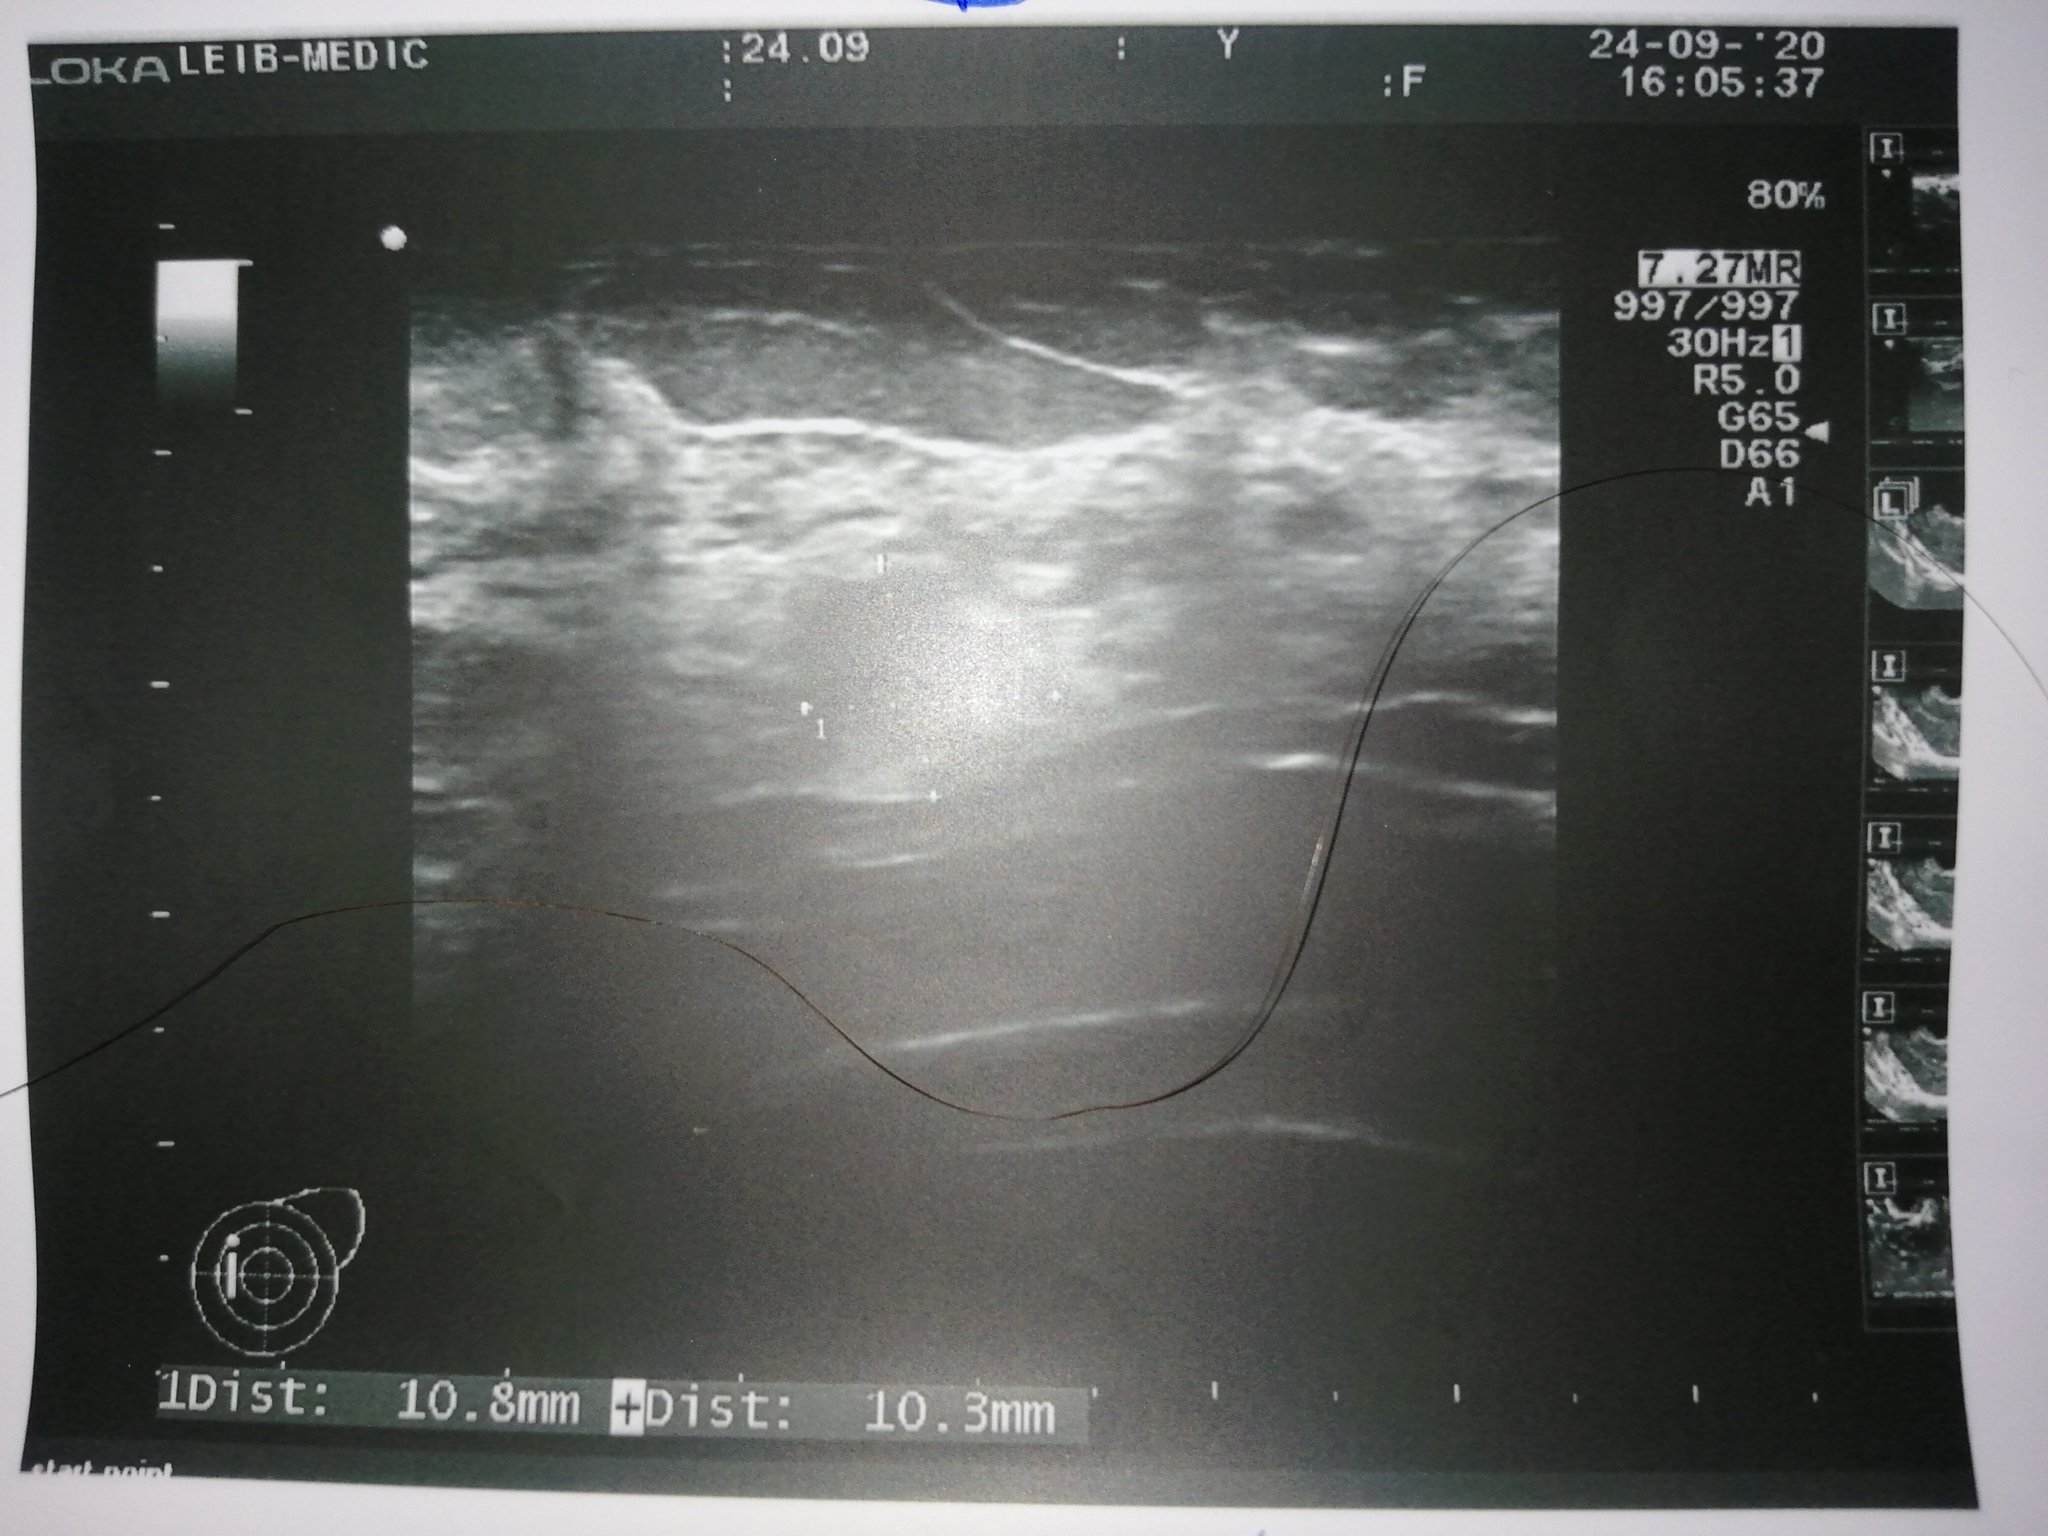

Фото как на УЗИ выглядит киста, фиброаденома и рак молочной железы . У кисты и фиброаденомы горизонтальный размер - больше вертикального, а контур — чёткий .

На УЗИ рак молочной железы отображает размеры, место расположения, стадию болезни . Опухоль можно даже выявить случайно при профосмотре, причём на 1 стадии .